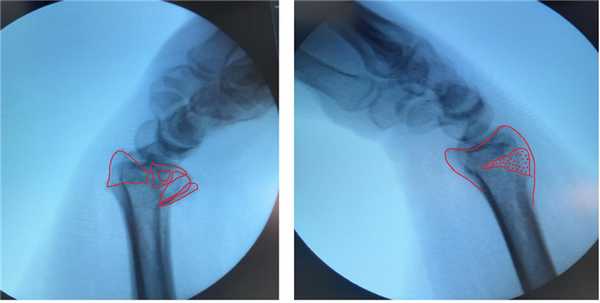

Намного более отчётливо степень нестабильности этих костных фрагментов видна под ЭОП-ом при выполнении функциональных проб. При тыльном сгибании определяется значительное количество мелких фрагментов тыльной кортикальной пластинки и внутрисуставной, оскольчатый характер перелома.

В такой ситуации лечение консервативным способом, гипсовой повязкой, не может дать надёжного результата. При оскольчатом характере перелома с дефектом тыльной кортикальной пластинки у дистального метаэпифиза просто нет надёжной опоры, и в итоге происходит усугубление смещения, суставная поверхность ещё больше наклоняется в тыльную сторону.